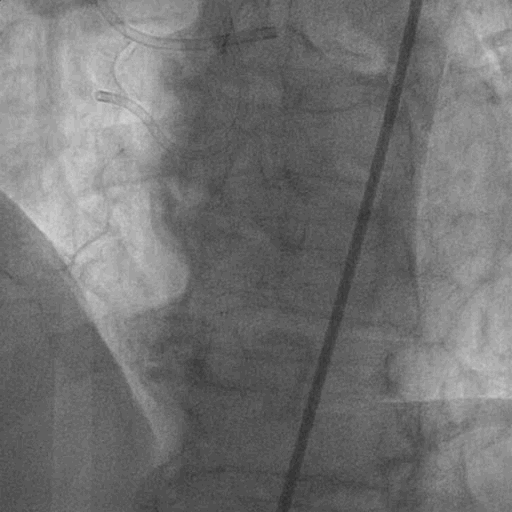

术前造影:

双侧造影:

左冠造影:

右冠造影: